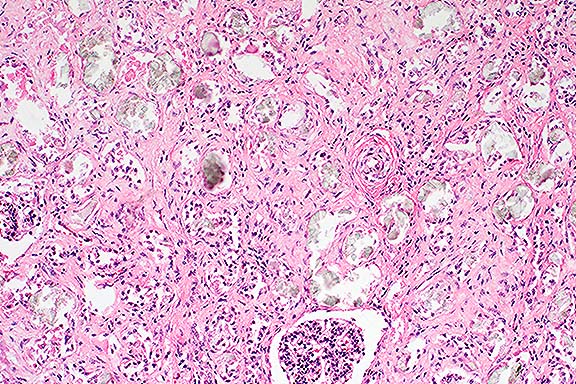

Case 2. Kidney. Note refractile crystalline material replacing tubular epithelium.

Case 2 Kidney. Polarized light. Note anisotropic crystals within degenerate tubules and interstitium.

Contributor's Diagnosis and Comments: Nephron loss, degeneration and necrosis, stromal fibrosis, diffuse, severe, oxalate crystals and chronic tubulointerstitial nephritis.

Gross and histopathologic findings, age, and breed of the calves are diagnostic for congenital/primary renal oxalosis, a condition similar to those reported in humans as an inherited metabolic disease. Secondary renal oxalosis in any age ruminant can be precipitated due to ingestion of plants containing high levels of oxalate, a circumstance ruled out in these two calves.

Kidney: Degeneration, necrosis, and loss, tubular, diffuse, severe, with intraluminal oxalate crystals, diffuse moderate interstitial fibrosis, and multifocal mild lymphocytic interstitial nephritis, Beefmaster, bovine.

Some of the conference participants observed an increased tortuosity of interlobular arteries in this case. There was discussion concerning whether this finding was due to an overall increase in the length of these vessels or was a result of the marked interstitial fibrosis and cortical loss.